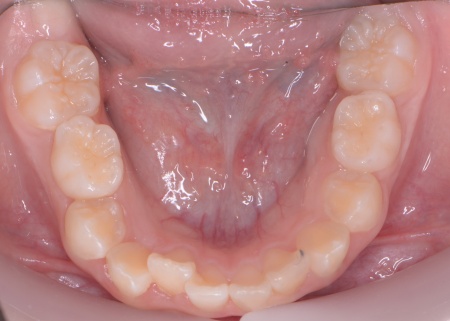

| カウンセリング | 拝見したところ、上の犬歯が歯列の外側に飛び出すように生えている、いわゆる八重歯でした。 さらに、上下の歯全体がデコボコに生えている「叢生(そうせい)」と呼ばれる状態で、これは歯が正しい位置に並ぶためのスペースが不足していることが原因だと考えられます。 このまま放置して顎の成長が完了してから矯正治療を行う場合、歯を並べるスペースを確保することが難しく、永久歯を抜く処置が必要になるケースがあります。 以上のことから、今の段階で歯並びを整える治療が必要だと診断しました。 |

患者様のご家族は「将来的な抜歯はできるだけ避けたいので、今のうちに治療をしたい」と希望されたため、成長期の段階で歯列を広げ、歯が並ぶスペースを確保する小児期の矯正治療「1期矯正」を提案しました。

メリット デメリット また、治療にあたりお口全体のバランスを確認したところ口元の突出はなく、顎のサイズはやや小さめですが、成長期であることから歯列の拡大が可能な状態だと判断しています。 以上の内容について丁寧に説明し、治療に同意いただきました。 まず、上顎に顎の骨を広げるための固定式の矯正器具「急速拡大装置」を、下顎には歯並びの幅を広げるための「リンガルアーチ」を装着します。 次に歯の位置を整えるため、ワイヤー矯正を開始します。 最後に、歯並びが整って見た目や噛み合わせにも問題がないことを確認し、装置を取り外して第1期矯正治療を終了しました。 現在も経過観察を継続していますが、歯が元の位置に戻る後戻りも見られず、残っている乳歯から永久歯への生え変わりも順調に進んでいます。 |